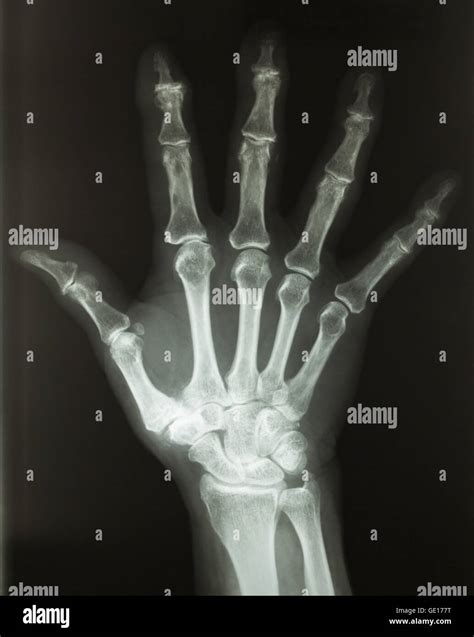

Interpreting the Radiographic Findings

When a physician analyzes an X Ray Normal Hand, they follow a systematic checklist to ensure nothing is overlooked. A "normal" report does not just mean "no broken bones"; it implies that the anatomy falls within the expected physiological range. The assessment typically involves evaluating the following criteria:

• Joint Space Symmetry: Ensuring that the cartilage-covered spaces between bones remain uniform and show no narrowing, which could indicate arthritis.

• Trabecular Pattern: Examining the internal, lattice-like structure of the bone. A normal X-ray shows a consistent, dense pattern without any dark spots or abnormal lesions.

• Alignment: Checking that the bones are not tilted, rotated, or shifted in a way that suggests ligamentous injury.

• Soft Tissue Shadows: While X-rays are primarily for bones, a skilled professional also checks the surrounding soft tissues for swelling or shadows that could suggest a hidden injury or foreign body.